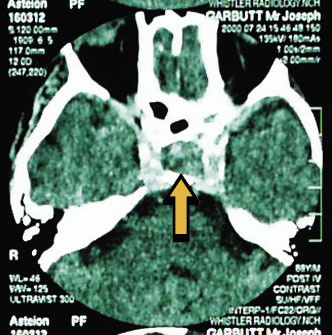

A presumptive diagnosis of pituitary apoplexy was made, and the patient was commenced immediately on intravenous fluids and hydrocortisone 100 mg, 12-hourly. The CT scan (Box, B) confirmed the diagnosis, showing a pituitary tumour measuring 12 mm in diameter. The salient feature is the variegated appearance, suggesting haemorrhage within the tumour.

In patients presenting with the constellation of collapse and gaze palsies, a diagnosis of pituitary apoplexy should be considered. The mechanism of third-nerve palsy is illustrated in the Box (C). The condition is life-threatening, but responds well to appropriate treatment. After the patient had undergone hypophysectomy, the gaze palsies took about three months to resolve completely. The patient remains active on pituitary replacement therapy only.